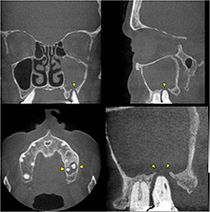

Dentogene Sinusitis der Kieferhöhle links durch eine Entzündung im Bereich einer Zahnwurzelspitze mit Zerstörung des umgebenden knöchernen Kieferhöhlenbodens (Digitale Volumentomographie, DVT)